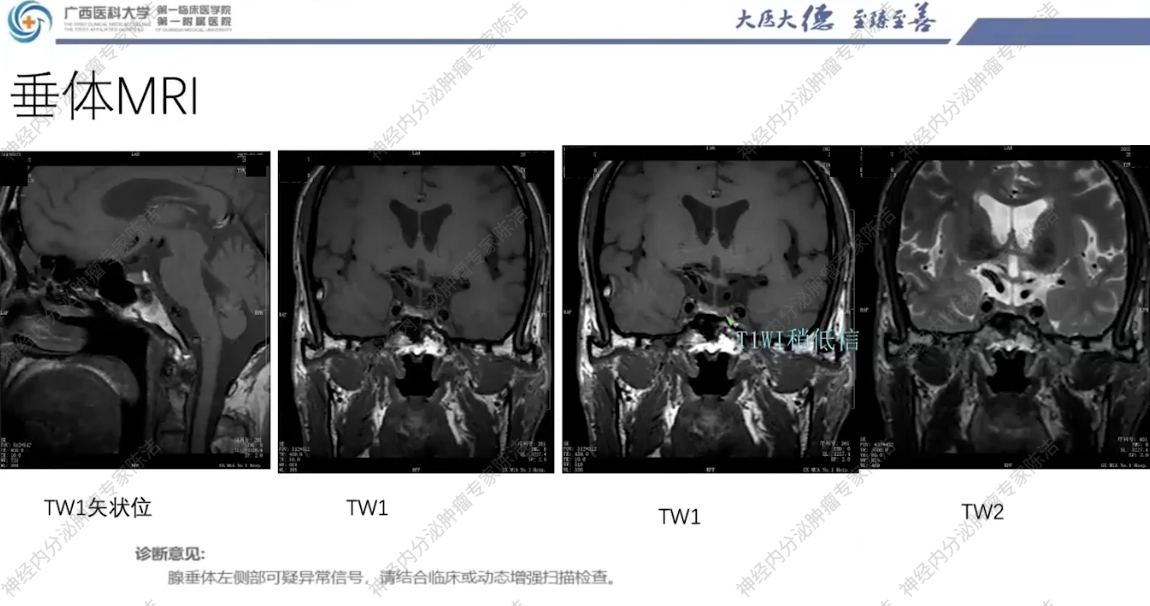

垂体MRI:提示垂体左侧部可疑异常信号,考虑垂体微腺瘤可能。

影像诊断科汤伟教授:影像学上,患者双肺多发结节,边界清晰,高度怀疑为转移瘤。腹部CT可见肠管明显扩张积气,呈肠梗阻样改变,符合巨结肠的表现。双侧肾上腺可见富血供的占位,符合嗜铬细胞瘤。垂体MRI平扫虽未做增强,但冠状位可见垂体左侧有低信号微腺瘤的可能,建议行垂体薄层动态增强扫描以明确诊断。